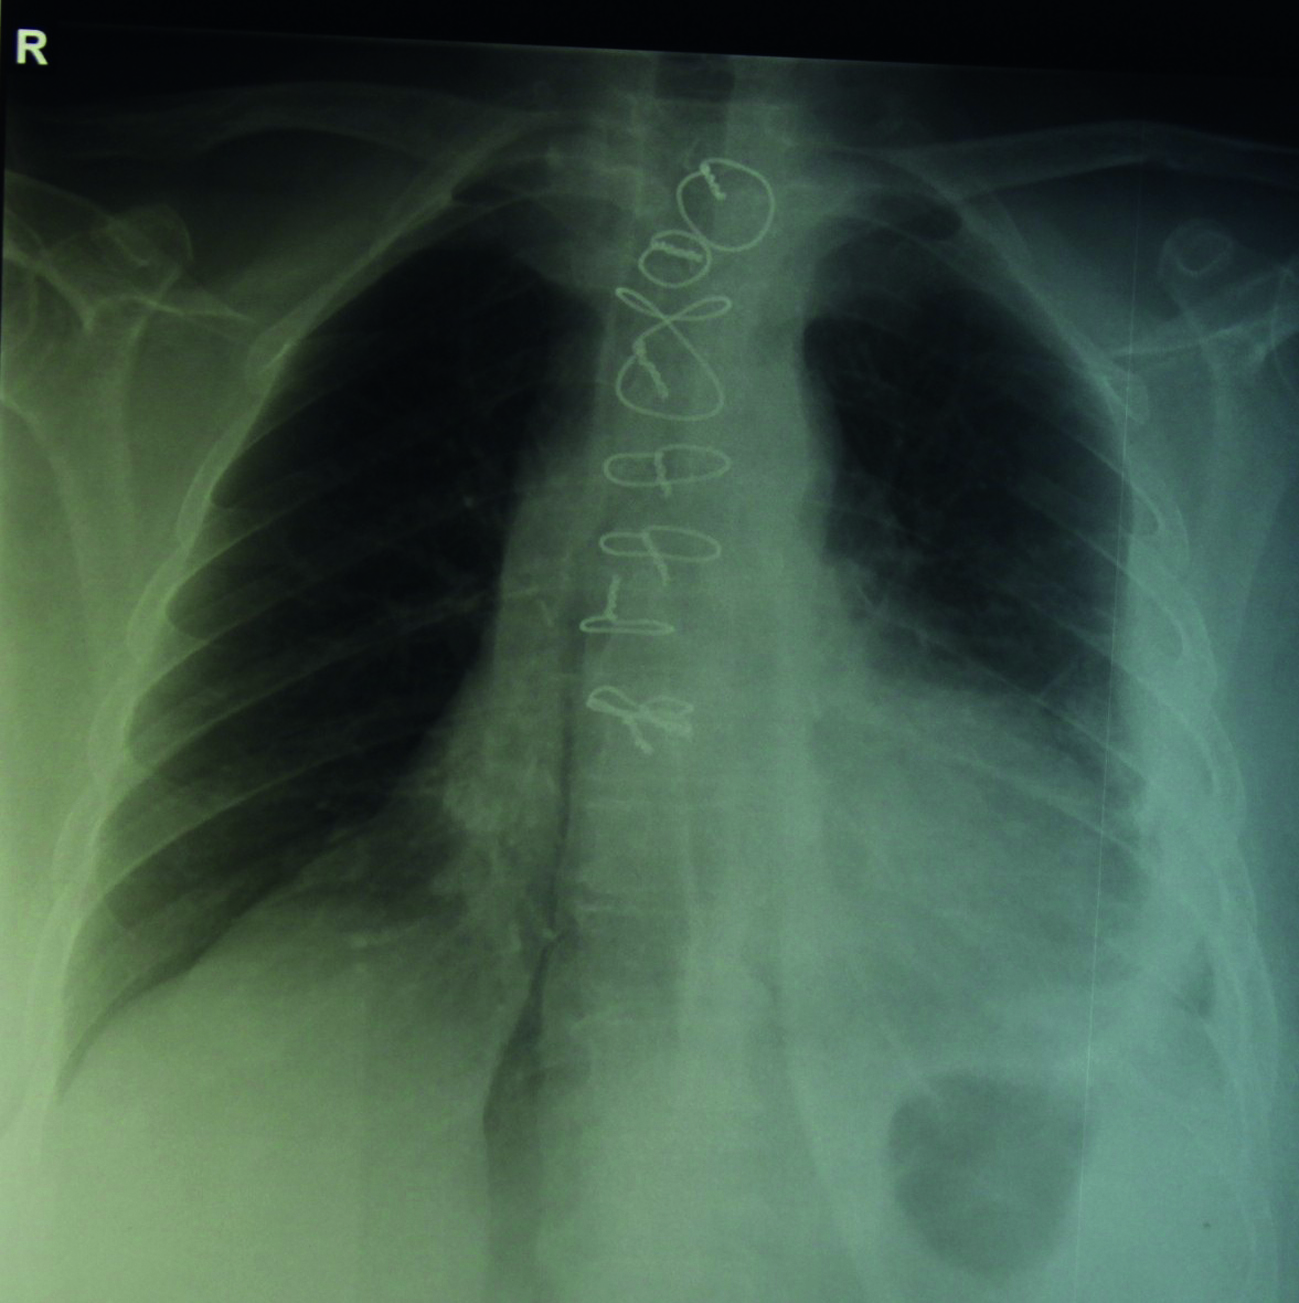

Рентгенологическим признаком наличия медиастинита мы считали расширение тени средостения, выявленное при обзорной рентгенографии ОГК (рисунок 1).

Рисунок 1. Обзорная рентгенограмма ОГК. Отмечается расширение тени средостения при постстернотомном медиастините.

Figure 1. Chest X-ray. An expansion of the shadow of the mediastinum with poststernotomy mediastinitis.

Данный симптом был выявлен у 5 (31%) пациентов первой группы. Интраоперационно медиастинит в виде наличия фибрина, детрита или экссудата был выявлен у всех 16 пациентов.